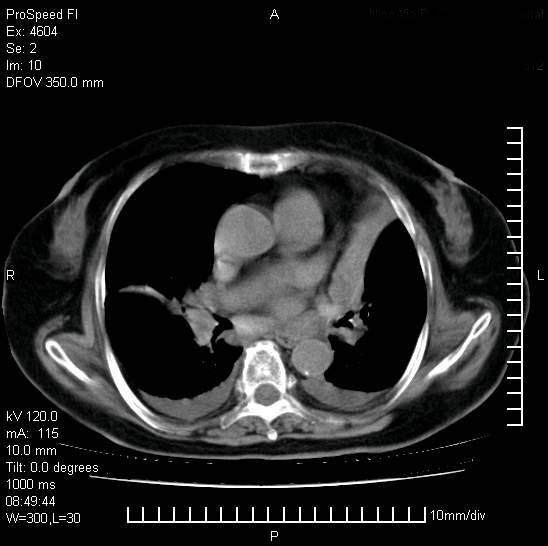

十几年前曾患肺结核,一周前突咳血约100ml,中性粒细胞稍高,诊断两上肺陈旧结核,下肺炎症,给予抗炎治疗,近几日晚上高热,39度,仍咳少量血,4天前ct及今天ct上传。

[face=黑体]8月30日[/face]

今天ct

支持陈旧性肺结核并两下肺感染,两侧胸腔积液。

短短几天内,病变范围明显增多扩大,以左侧明显,而且双侧出现胸水,还是考虑感染.

短短几天内,病变范围明显增多扩大,以左侧明显,而且双侧出现胸水,我更多考虑左侧中心性肺癌并并阻塞性不张及肺炎,炎症变化也太快了!

1)两肺结核并感染。2)不排除左肺上叶中央型肺癌并阻塞性肺炎、肺不张可能;建议行纤支镜检查。3)右肺门及纵隔淋巴结肿大。4)双侧胸腔积液。